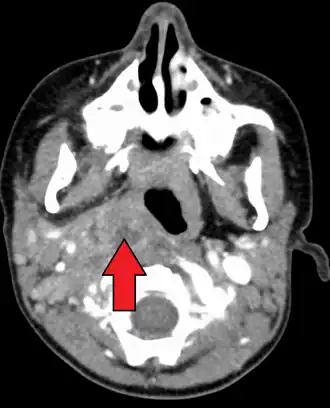

Large retropharyngeal abscess as seen on CT -

Large retropharyngeal abscess as seen on CT

A computed tomography (CT) scan is the definitive diagnostic imaging test.[4]